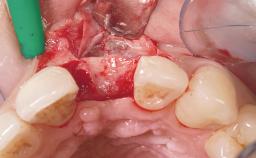

Immediate Placement of an Implant in a Maxillary Left Central Incisor Site

A 33-year-old female patient presented with an upper left central incisor that required extraction after a failed endodontic therapy. The tooth had been traumatized when the patient was a teenager and had undergone several endodontic treatments, including two apicectomy procedures. The patient was in good health and did not smoke. Clinical examination showed that the patient had a high lip line. In full smile, the gingival margins of the upper teeth were visible to the first molars. The gingival margins of central incisors 11 and 21 were only just showing. Examination of tooth 21 confirmed that the tooth was mobile and had hypererupted by 1 mm.